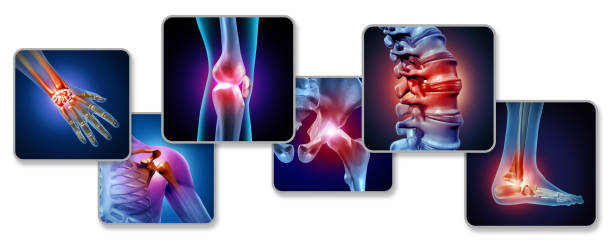

관절은 두 개 이상의 뼈가 모이는 지점을 말한다. 관절은 움직임을 가능하게 하고 골격계에 구조적 지지를 제공하는 데 꼭 필요한 요소이다.

관절은 두 개 이상의 뼈가 만나는 신체의 구조로 움직임을 허용하고 지원한다. 관절은 이동성에 매우 중요하며 골격계에 유연성, 안정성, 보호 기능을 한다. 몸 전체에서 존재하며 구부리기, 비틀기, 회전과 같은 다양한 유형의 움직임을 가능하게 한다.

관절은 움직임을 촉진하고 안정성을 제공하며 과도한 마모로부터 뼈를 보호함으로써 신체에서 중요한 역할을 한다.